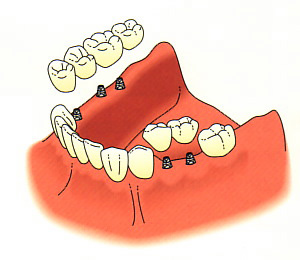

This is how the finished result would look.

Dental implants are very effective on the lower arch, where a removable partial denture might be considered. By using implants, a better bite is possible, as well as better stimulation to the bone.

Here is an example of how a lower implant case might look.